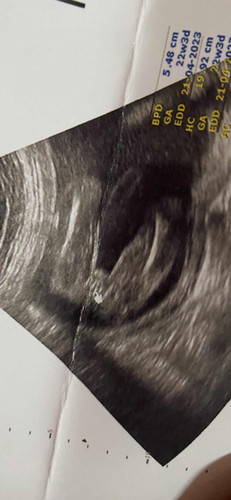

แบบนี้ผู้หญิง100%ไหมคะ พอดีคนข้างบ้านบอกว่าหมอบอกว่าผู้หญิง100%แต่ออกมาเป็นผู้ชาย😂

ญ ชัวค่ะ เป็นกลีบขนาดนี้ แบบนี้ชายค่ะ